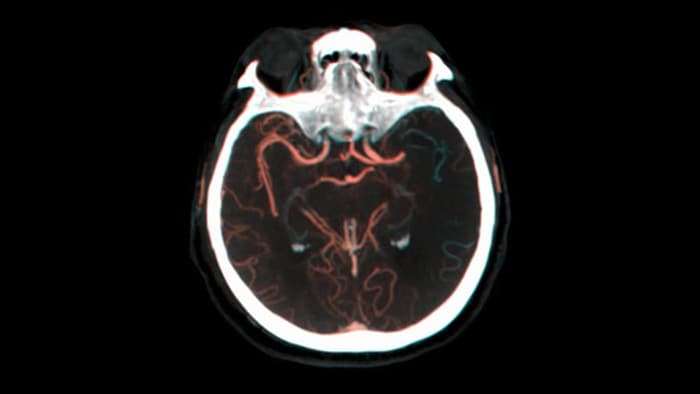

SmartCT Soft Tissue genereert een CT-achtige visualisatie van weke delen en ondersteunt diagnoses van beroertes op drie manieren. Een scan zonder contrastverbetering helpt bij de detectie van vroege ischemische veranderingen, een scan in een vroeg stadium helpt bij de identificatie van de proximale occlusie, en een scan met contrastverbetering in een laat stadium ondersteunt de detectie van collateralen.